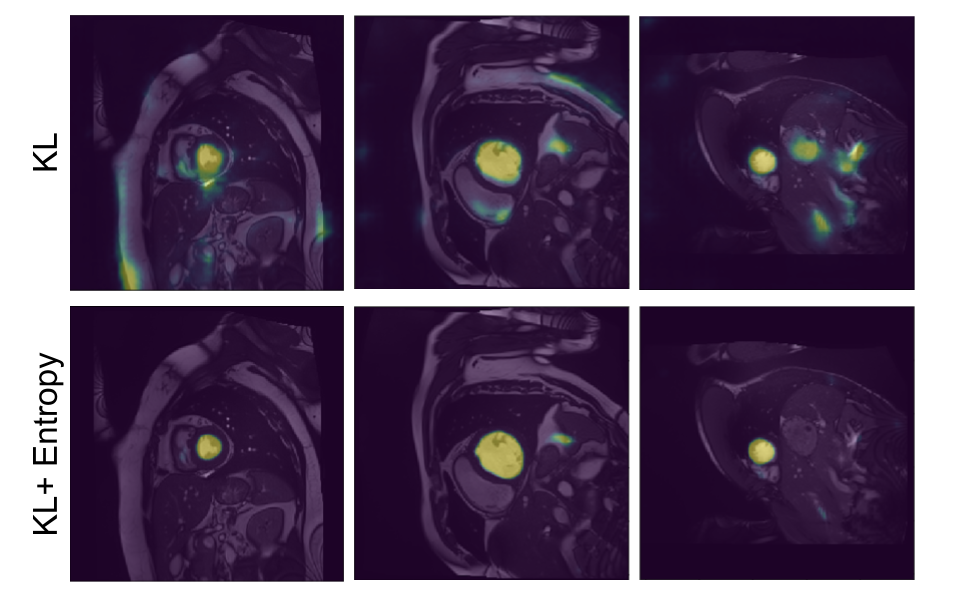

Refer to caption

Figure 9: Probability maps obtained by the proposed KL𝐾𝐿KL and KL+Ent𝐾𝐿𝐸𝑛𝑡KL+Ent models.

In addition to the numerical results presented before, we also depict qualitative results in Fig. 8 and Fig. 9. Particularly, Fig. 8 depicts the segmentation results for the models evaluated in Table 1. We see that results obtained by models with a single network typically under-segment the object of interest (first row) or generate many false positives (second row). Decoupling the decoding branches might reduce the false positive rate, however, it also tends to under-segment the target. Finally, we observe that both of our formulations achieve qualitatively better segmentation results, with the KL+Ent model yielding segmentations similar to those generated by the upper bound model. Furthermore, in Fig. 9, we illustrate additional qualitative results of our models. We observe that without the entropy term our model produces less confident predictions, which results in more noisy segmentations.